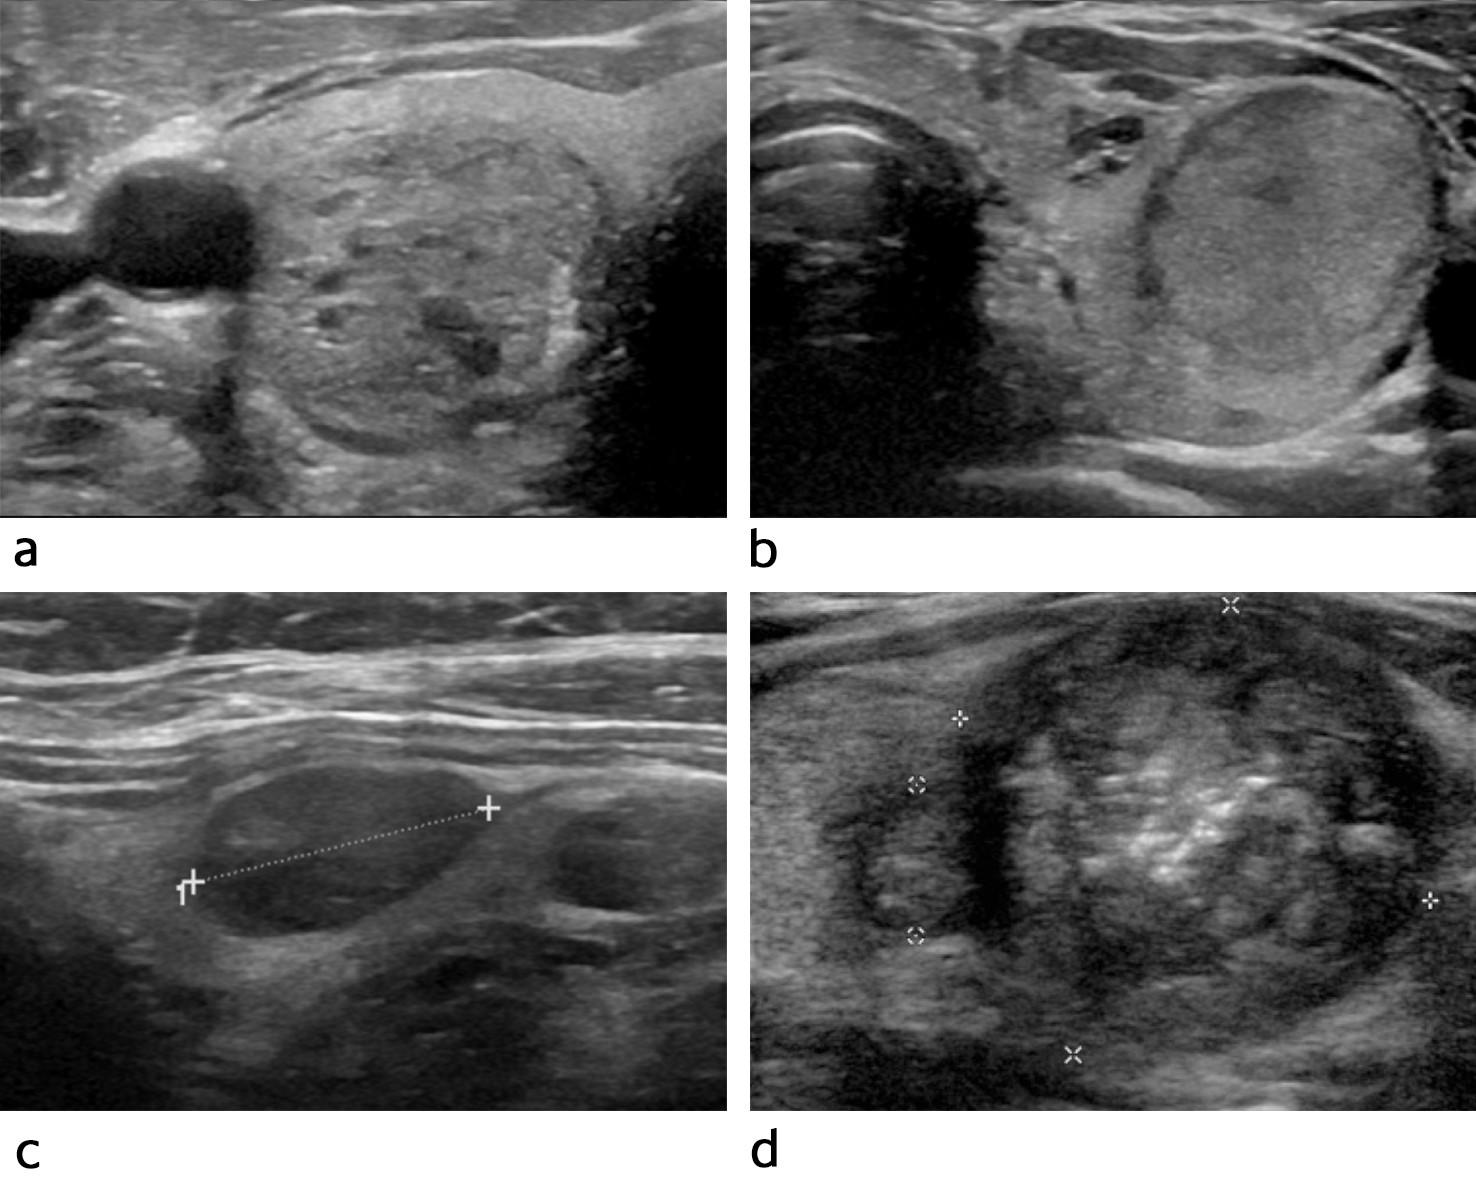

En typisk benign tyreoideaknute har et cystisk eller spongiøst (svampaktig) preg, er velavgrenset og har oval form (figur 1a). Hvis pasienten har flere ensartede og velavgrensede knuter i en forstørret kjertel, er disse som regel benigne og undersøkes ikke nærmere cytologisk. Kontroll med ultralydundersøkelse utføres kun dersom det tilkommer symptomer eller funn som er alarmerende (ramme 2).

Malignitetssuspekte tyreoideaknuter er gjerne solide og lav-/hypoekkogene, har uregelmessig avgrensning og irregulær form og kan inneholde mikroforkalkninger (figur 1d). Disse knutene må undersøkes videre med finnålscytologi.

TIRAD er et oversiktlig rapporteringssystem som kan heve kvaliteten på ultralydundersøkelsene (tabell 1, figur 1). Systemet kan også bidra til å redusere overdiagnostikk. Vi vil foreslå at EU-TIRAD brukes som standard ved besvarelse av ultralydundersøkelse av tyreoidea. ACR-TIRAD er imidlertid likeverdig, og finnes også som en enkel nettbasert kalkulator (15). Det bør komme frem i svaret hvilket system som er benyttet.